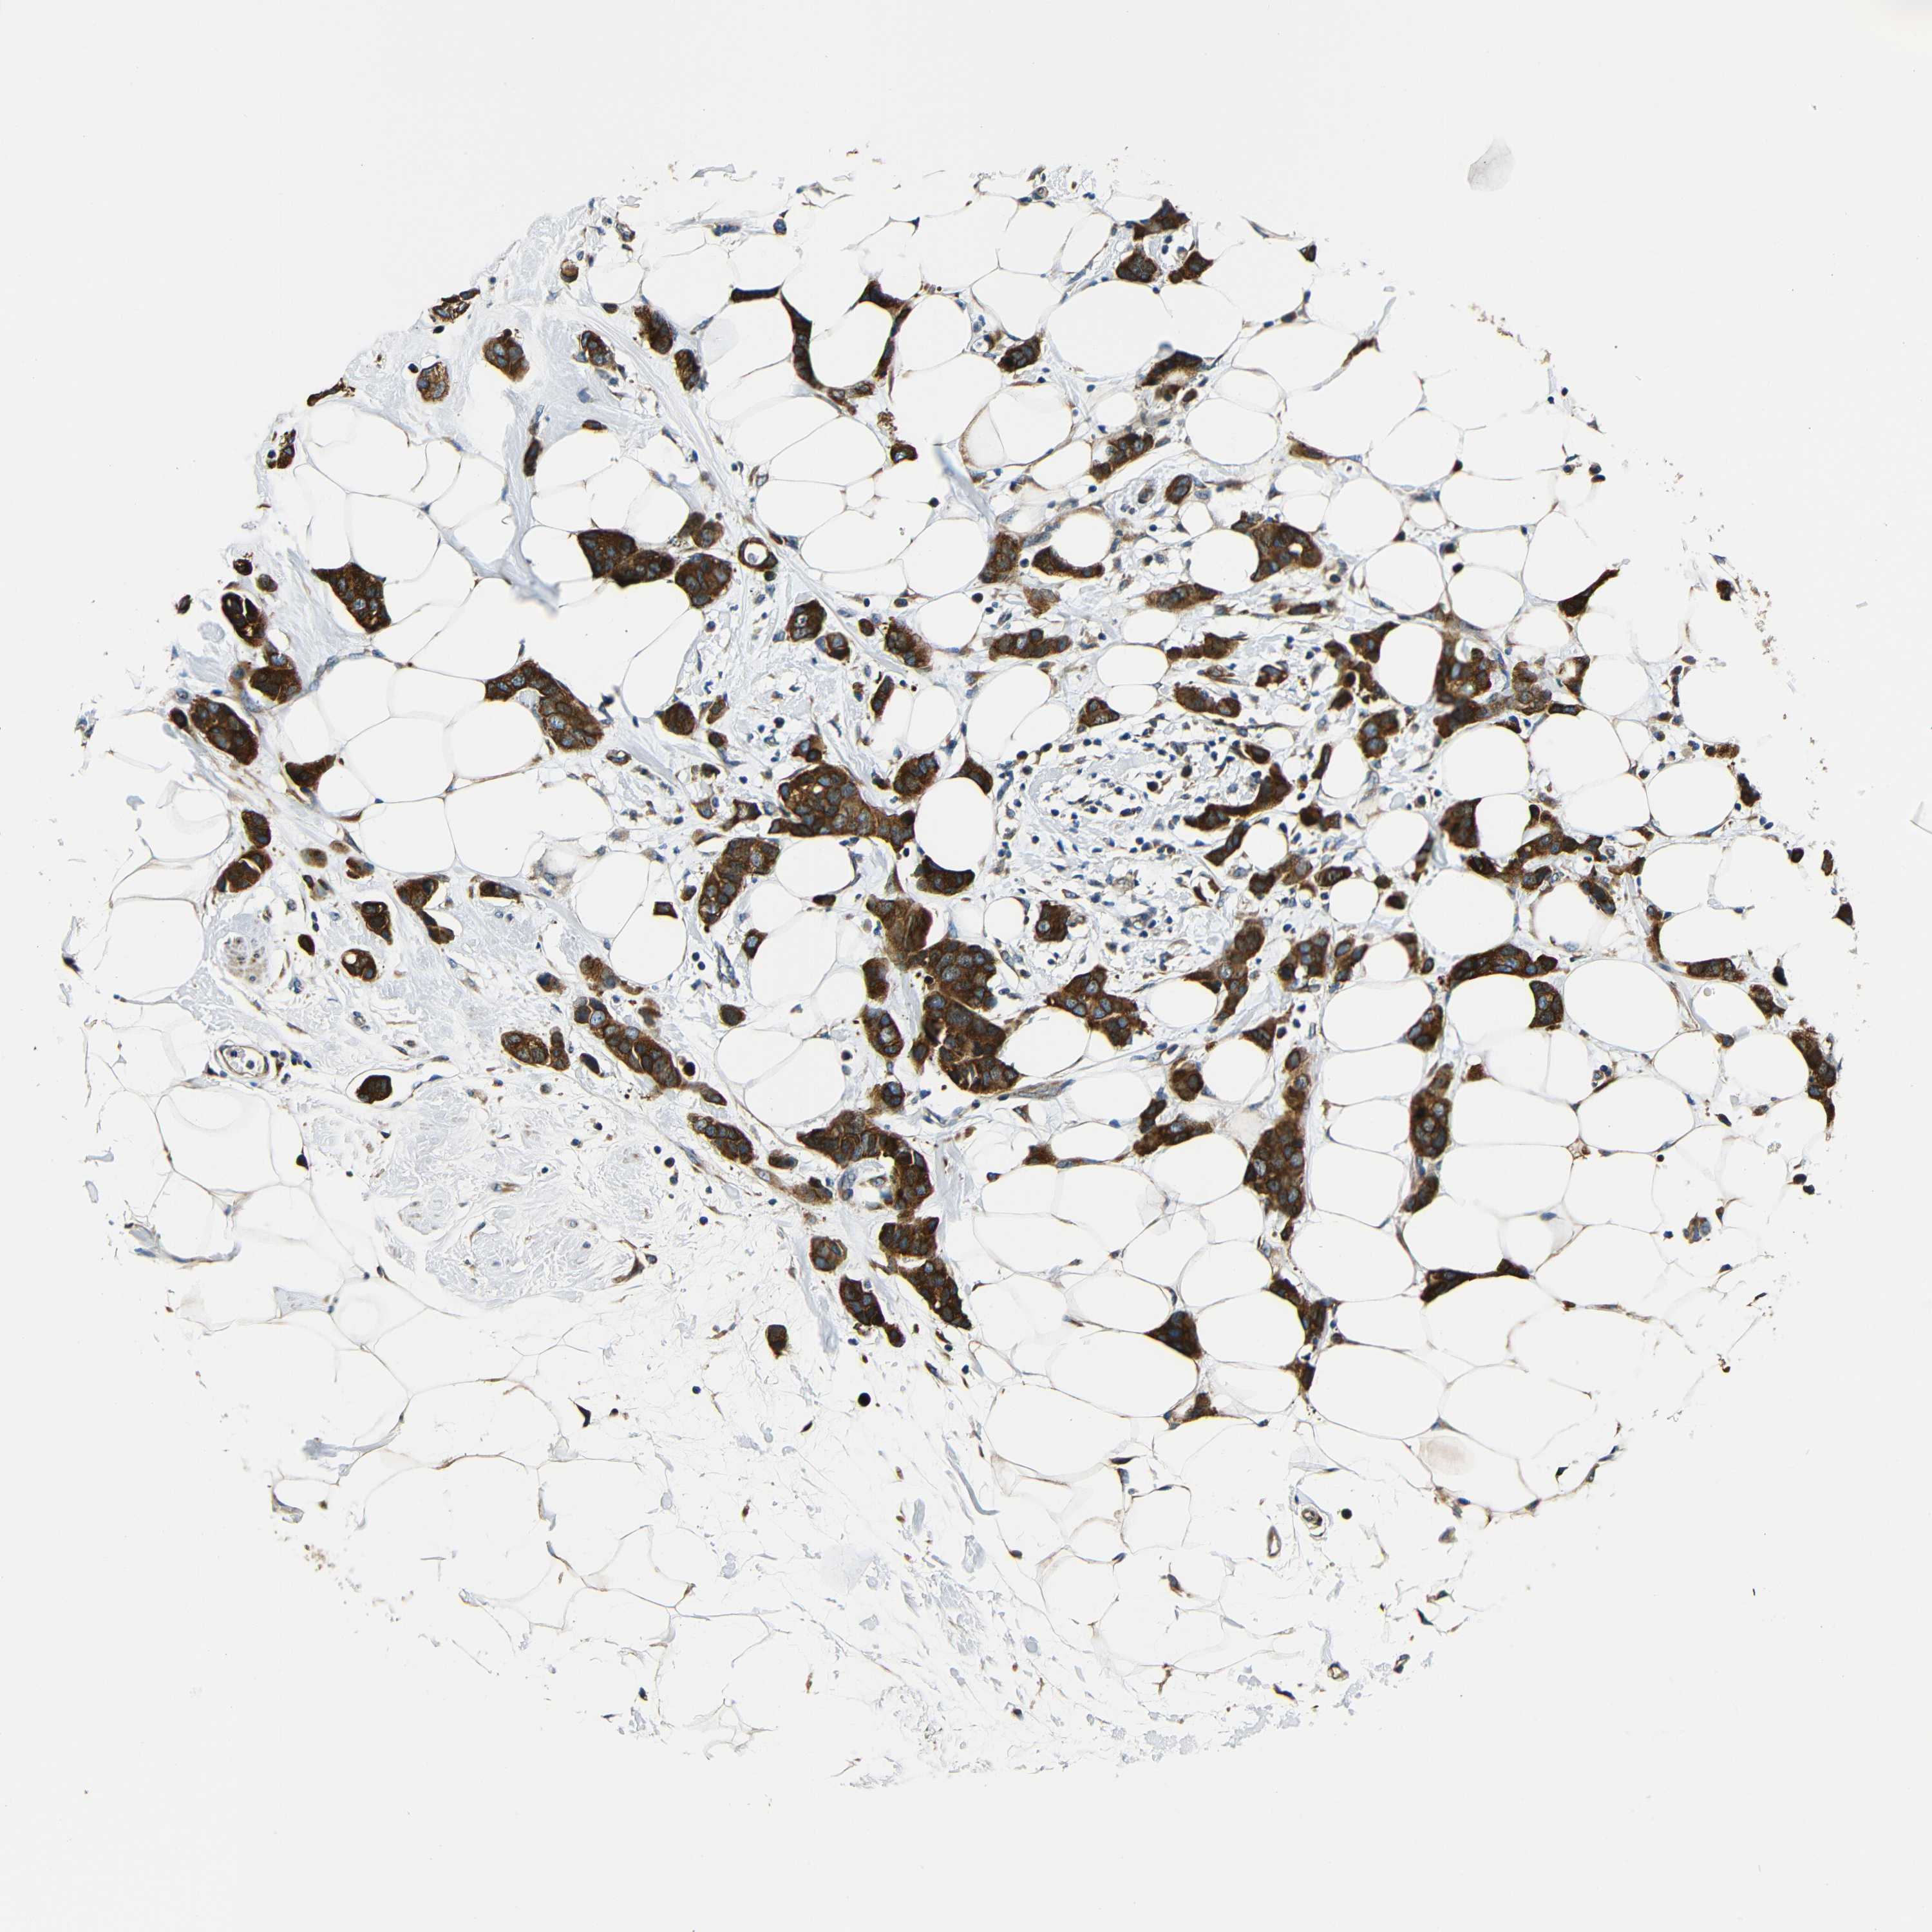

Breast cancer

Human cancer